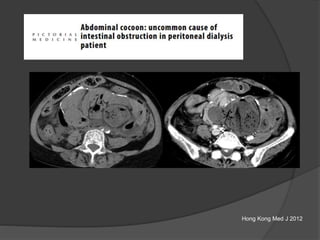

Peritoneal carcinomatosis

Thick enhancing membrane around a

conglomerate of small bowel loops in

the center “cocoon”

Dilated proximal colon

Diagnosed with adenocarcinoma lung 6 months ago

Case 2 Diagnosis: “Cocoon

peritonitis”

•AKA sclerosing

encapsulating peritonitis

•Rare cause of bowel

obstruction due to fibrotic

encapsulation of the bowel

forming a sac or cocoon

•May be idiopathic or

secondary to chronic

peritoneal dialysis, TB,

sarcoidosis, GI malignancy,

fibrogenic foreign material

•Treatment –Surgical

removal of the covering

membrane

Hong Kong Med J 2012